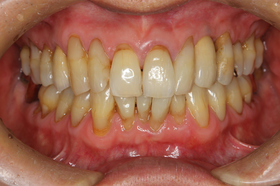

最終的な上部構造として、下の写真のようにメタルセラミックスクラウンを装着しました。

左が術後で、右が術前です。

術前は、犬歯部の歯肉が著しく退縮(下がっている)していましたが、GBRや結合組織移植を併用することで、周囲と調和した歯肉形態に回復することができました。

きれいになったと患者さんにも喜んでいただき、紹介していただいた娘さんの気持ちに応えることができて何よりです。